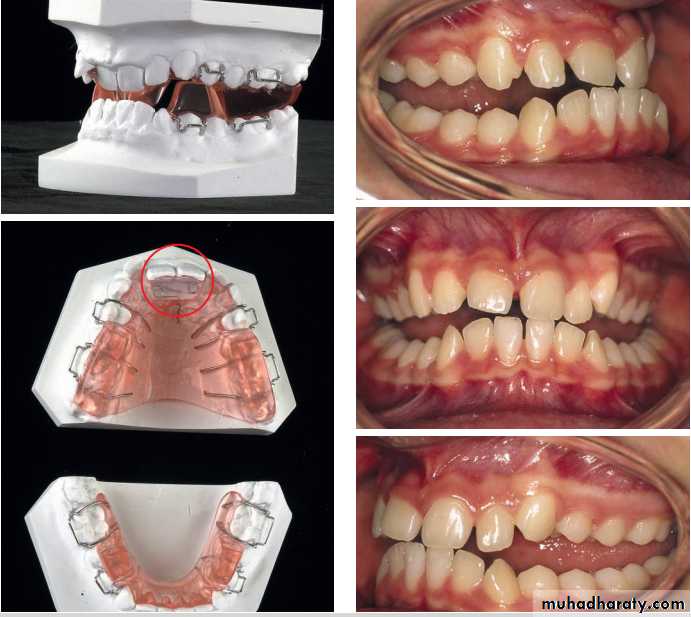

TWIN BLOCK APPLIANCE

• The Twin Block appliance is a removable, orthodontic functional appliance that is used to help correct class II div. I, particularly an underdeveloped lower jaw.The removable twin block is a tooth-born functional appliance that is worn fulltime. It helps in the advancement of the mandible. It is a two-piece appliance composed of an upper and lower bite block. Upper & lower bite blocks interlock at 70 0 angle.

The upper and lower parts fit together using posterior bite blocks with interlocking bite-planes, which posture the mandible forwards. The blocks need to be at least 5 mm high, which prevents the patient from biting one block on top of the other. Instead the patient is encouraged to posture the mandible forwards, so that the lower block occludes in front of the upper block. The appliance can be worn full time, including during eating in some cases, which means that rapid correction is possible. It is also possible to modify the appliance to allow expansion of the upper arch during the functional appliance phase. A modification to allow

correction of Class II division 2 malocclusions

Twin-block appliance modifi ed for treatment of a Class II division 2 malocclusion